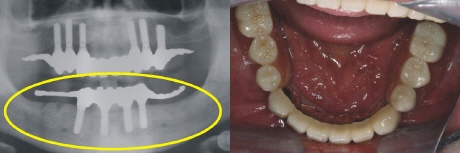

Versorgung

Nach der Einheilzeit werden auf die Implantate Teleskopkronen aufgesetzt, über die der Zahnersatz gesteckt wird (Oberkiefer).

Nach der Einheilzeit werden auf die Implantate Teleskopkronen aufgesetzt über die der Zahnersatz gesteckt wird (Unterkiefer).

Die fertige Arbeit ermöglicht auf den sechs Teleskopen im Oberkiefer eine rein kieferkammbegrenzte, also gaumenfreie Versorgung. Das Röntgenbild links zeigt die solide Konstruktion, die eine reine Kaukraftweiterleitung in den Kieferknochen ermöglicht.

Auch im Unterkiefer ist der Zahnersatz auf den Kieferkamm begrenzt und ermöglicht so höchsten Tragekomfort.